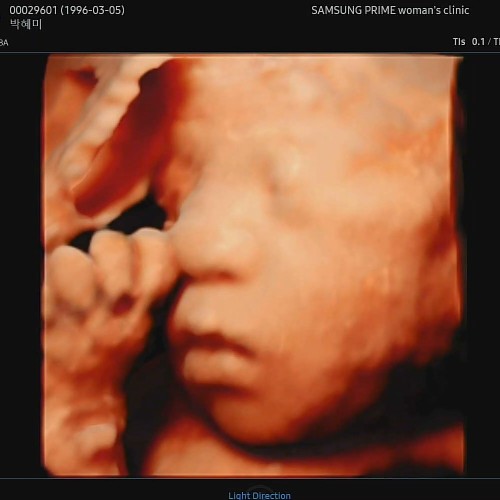

우리아가 첫모습!

벌써 중기에요. 콩알모양의 아가 모습이 엊그제 같은데요. ...